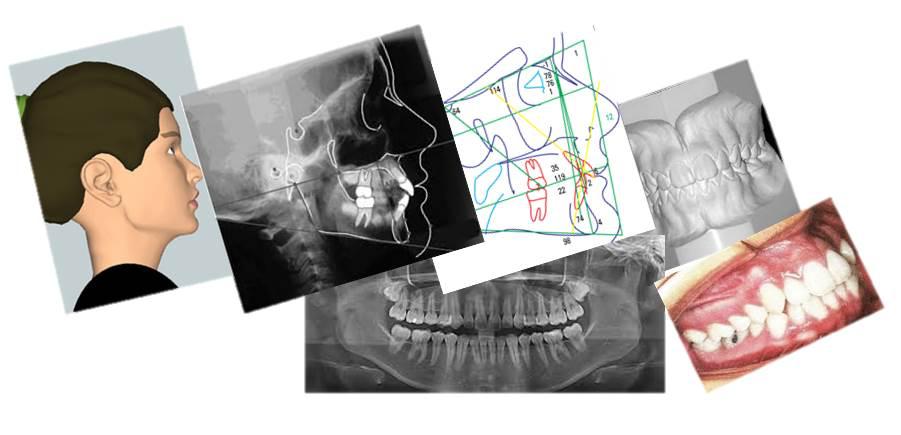

Documentação dentária

A documentação ortodôntica é um conjunto de exames composto por radiografias, fotografias intra e extra-bucais, modelos em gesso das arcadas dentárias, análises cefalométricas e de modelos computadorizados que o dentista solicita para ter uma visão abrangente e detalhada do caso de seu paciente.